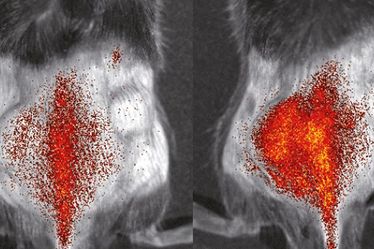

Bereits seit Jahren arbeiten die WWU-Forscher an Techniken, mit denen sie Dynamiken und Wechselwirkungen von Immunzellen in lebenden Organismen bestmöglich sichtbar machen können. Hierzu nutzen sie und ihre internationalen Kollegen unter anderem die Positronen-Emissions-Tomographie und die optische Bildgebung. Ein großes Ziel des jetzt anlaufenden Projekts ist es, geeignete Methoden zu entwickeln, mit denen Immunzellen vor, während und nach einer Immunbehandlung beobachtet werden können. Dabei sehen sich die Forscher die Vorgänge zunächst in tierischen Krankheitsmodellen an – mit dem Ziel, die Ergebnisse und Methoden zeitnah auf Patienten zu übertragen und letztendlich Immuntherapien bei Krankheiten wie Krebs oder Entzündungen „bildgesteuert“ zu verbessern.